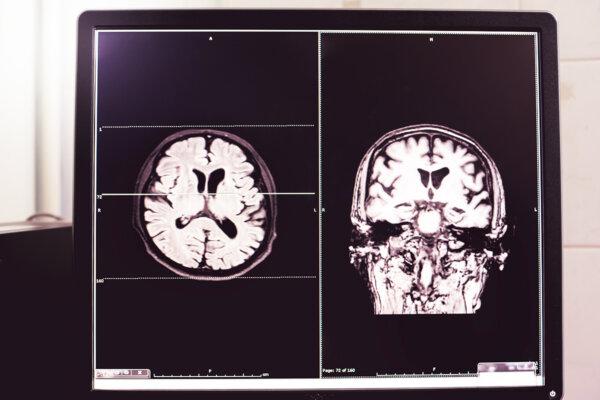

Dr. Counce also has several vaccinated patients who developed brain atrophy. One patient had hippocampal atrophy with symptoms of memory loss and personality changes.

Dr. Counce reasoned that if the hippocampus, which serves as the brain's memory center, atrophies, the adjacent limbic system, which processes emotions, may be similarly affected.